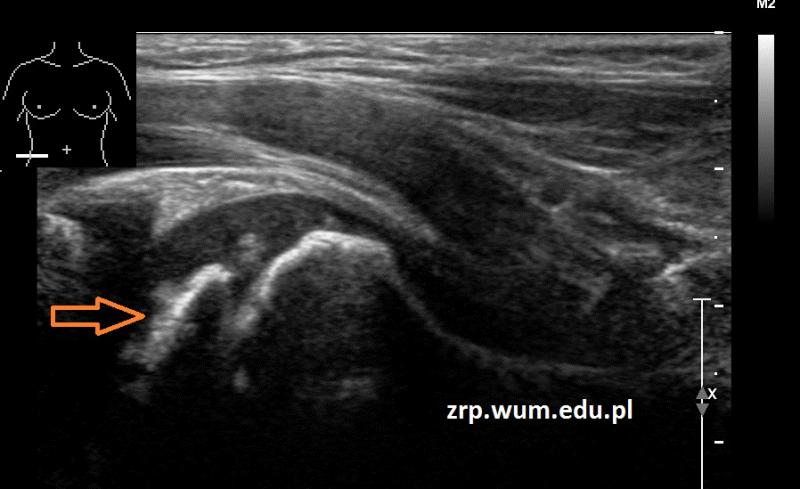

Rozpoznanie: W badaniu USG uwidoczniono spłaszczenie i nerówny zarys nasady głowy kości udowej prawej (pomarańczowa strzałka) - cechy ch. Perthesa. W wywiadzie - chłopiec miał kilka epizodów utykania w ciągu ostatnich kilku miesięcy. Dla porównania - prawidłowa głowa kości udowej lewej (zielona strzałka).